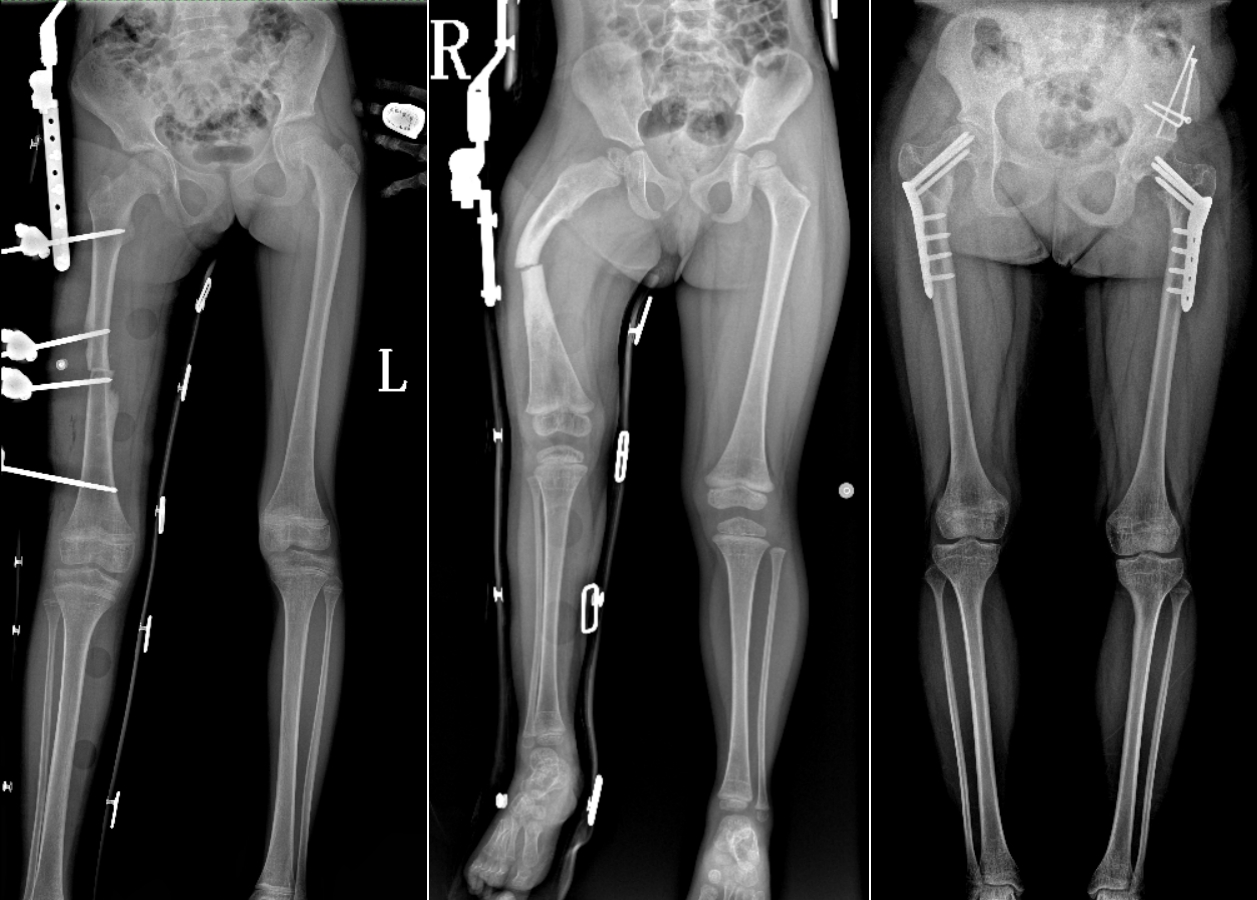

DR是臨床骨科的重要檢查手段之一。在骨科檢查中,脊柱矯形、長骨骨折、腰椎退行性病變等,需要采集脊柱、下肢全景圖像,輔助醫(yī)生臨床診斷,從而制定科學的治療方案,普愛醫(yī)療的大視野平板動態(tài)DR就像是一座橋梁,連接起現(xiàn)代醫(yī)療技術與當?shù)厝嗣竦尼t(yī)療需求。

普愛醫(yī)療自主研發(fā)的大視野平板動態(tài),采用17"*34"的有效視野,一次曝光即可得到全脊柱或全下肢影像。相較于多張攝影再軟件拼接的DR設備,PLX8600解決了拼接圖像存在密度不均勻,拼接處圖像配準和放大效應等問題,給臨床帶來了真正的大視野影像解決方案。

除了常規(guī)靜態(tài)攝影外,PLX8600的大平板具備動態(tài)透視和點片功能,能夠很好地觀察復雜部位病灶,有效地抓取關鍵幀,降低患者多次攝片的概率。如:全脊柱狀態(tài)評估、長骨關節(jié)活動度、下肢靜脈造影瓣膜功能評估、消化道功能評估、脊髓造影等更多大視野臨床應用,“多面手”都能輕松應對。